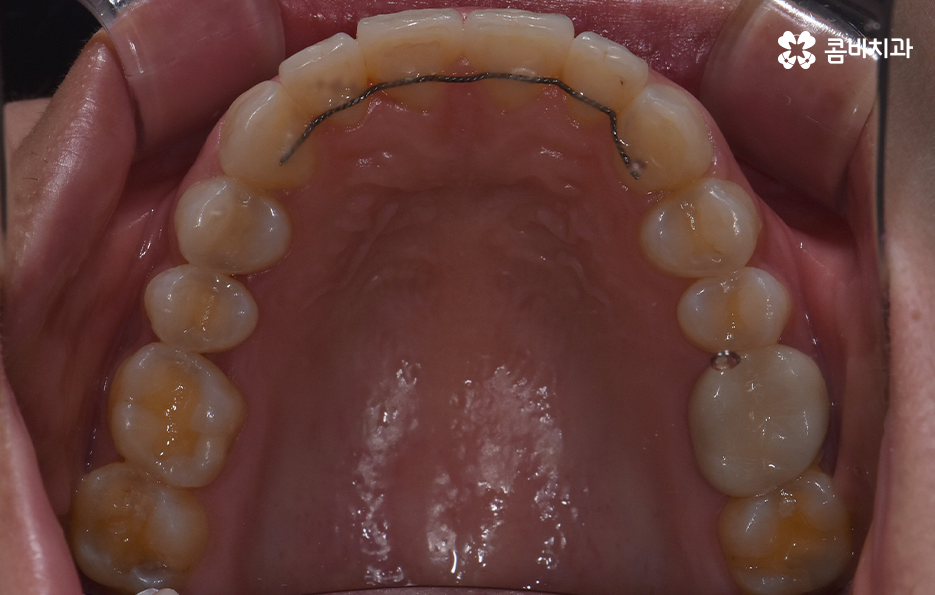

앞니 틀어짐 교정 방법 경미한 수준일 때는 부분 교정 방식은 치료 기간이나 방법 면에서 비교적 간단한 치료가 가능한데 앞니 6개 정도에만 브라켓을 부착해 미세한 틀어짐을 바로잡는 방식으로 치아가 크게 회전하지 않았거나 공간이 약간 부족한 정도라면 효과적이며 기간도 보통 3~6개월로 짧은 편으로 이 방식은 앞니 배열을 빠르게 정리하면서도 자연스러운 라인을 만들 수 있어요.

두 번째 방법은 투명 교정(인비절라인 등)으로 앞니만 틀어진 경우 투명 교정은 효율적이고 눈에 띄지 않아 일상생활도 편한데 경미한 앞니 틀어짐은 투명 교정이 자연스럽고 부담이 적은 방식으로 투명 교정으로 앞니를 조금씩 배열을 맞추는데, 특히 벌어짐이나 약한 회전 교정에 효과가 좋으며 이러한 방식은 투명교정 장치의 착용 시간이 중요하기 때문에 하루 20시간 정도 착용해야 원하는 속도, 결과가 나온다는 특징이 있어요.

부분교정과 투명교정 방식은 대표적으로 앞니 틀어짐이 경미한 수준일 때 적용하기 적합한 방식이지만 교합의 개선과 얼굴형의 변화를 목표로 해야하는 경우라면 환자 분들이 앞니만 고치는 것을 원한다고 해도 전체교정이 필요한 케이스도 많기 때문에 우선적으로 정밀검진을 통해서 나에게 적합한 치료 계획을 세우는 것이 중요하겠고 치아교정의 목적에는 치료 후의 지속성, 안정성 또한 함께 고려해야 한다는 점에서 앞니 틀어짐의 원인을 개선하여 재발을 방지하는 것까지도 잘 고려하실 필요가 있었어요

결론적으로 앞니가 틀어지는 이유는 생활습관, 구조적 문제, 뼈의 변화, 혀의 위치, 교합 등 다양하게 얽혀 있으며 특히 틀어짐이 경미할 때, 혹은 앞니의 변형이 시작되는 초기에는 비교적 간단한 교정 방법으로도 충분히 개선할 수 있고, 비교적 치료 기간도 짧아 부담이 적지만 중요한 것은 원인을 함께 해결해야 재발을 막을 수 있다는 점으로 무엇보다 나에게 적합한 치료 계획을 경험 많은 교정 전문의와 충분히 상의하여 판단하시길 바라고 있어요